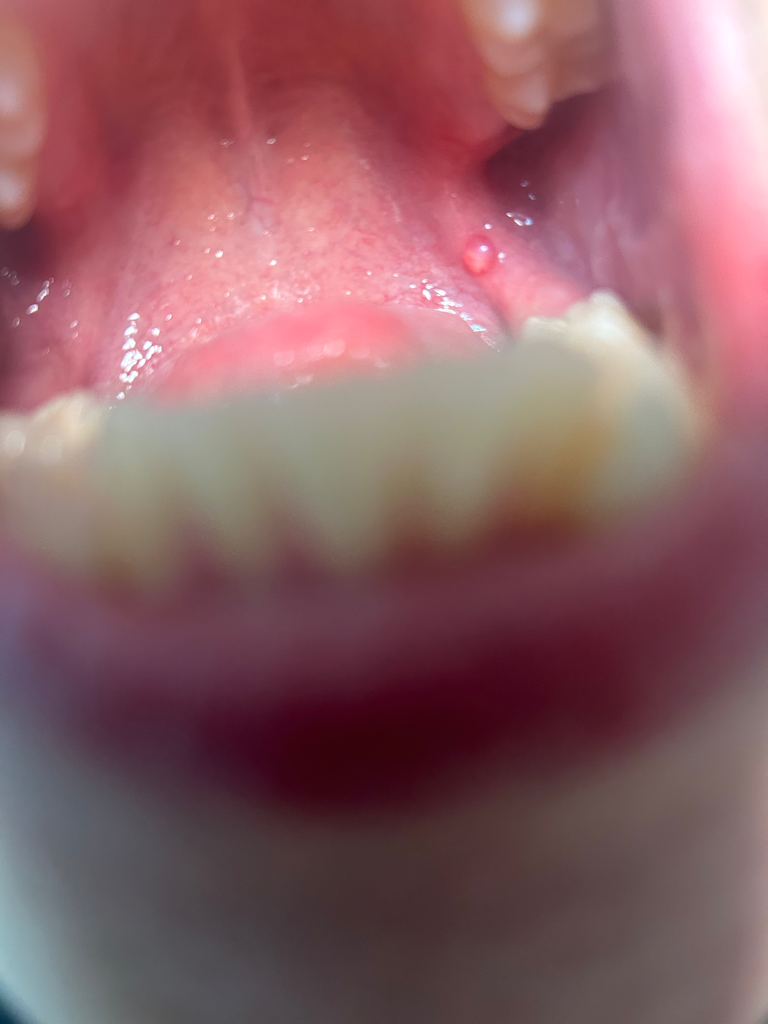

일단 구강암은 아닌것으로 보입니다.

구강과 혀 전반에 걸쳐 퍼져있는 병소가 만약에 암이라면 이미 말기암 일것임으로 말이 되지 않습니다.

거의 정상으로 보입니다만.

단수히 물집이 잡히신거 같습니다. 크게 문제가 잇는건 아니니 너무 걱정하지않으셔도 될것같습니다. 구내염증상이신거 같습니다 .

구강내 점막은 자극을 받거나 하면 점막에 변화가 생기기도 합니다.

구강암의 가능성은 매우 작지만 걱정이 되신다면 치과엣 진료를 받아 보는것이 좋습니다.